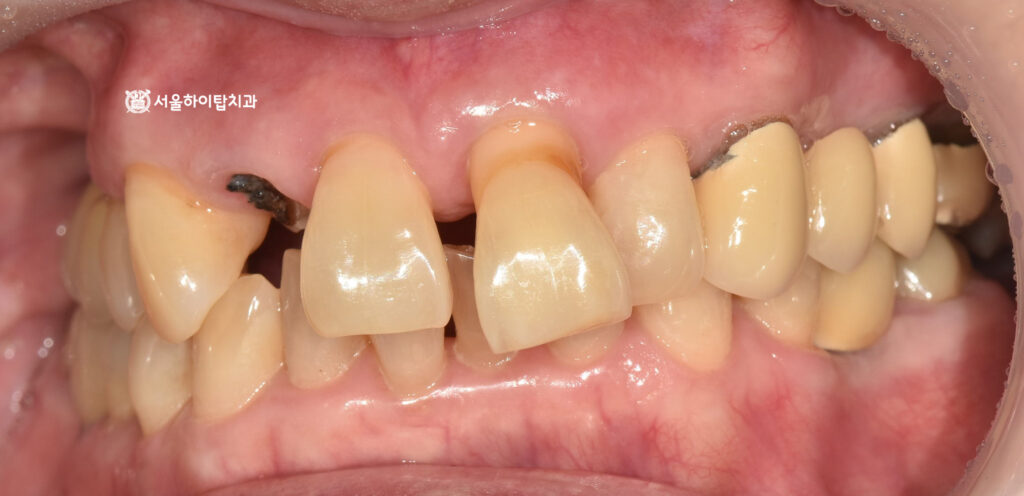

1. 초진

만수동 치과 에서 표시한 부분을 보면,

부러진 자연치와 일부 정출된

모습을 확인할 수 있습니다.

이러한 문제가 동시에 나타난 이유는,

충치로 인한 치질 약화와 골 소실이

함께 진행되었기 때문입니다.

이에 따라 구강 내 사진을 보면

충치로 인해 부러진 파절면이

뚜렷하게 관찰됩니다.

또한 뼈의 흡수로 인해

정출되고 앞니 사이가 벌어진